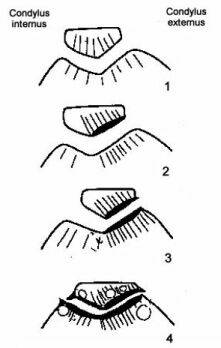

Определенная роль в диагностике поражений коленного сустава отводится бедренно-надколенниковым аксиальные проекциям. На этих проекциях соприкосновение бедренно-надколенниковых секторов варьирует в зависимости от того, как согнуто колено: на 30, 60 или 90° (рис.6).

Рисунок 6. Аксиальные снимки бедренно-надколенникового сустава.

а. - выполненный при сгибании колена на 30°;

б. - выполненный при сгибании колена на 60°;

в. - выполненный при сгибании колена на 90°.

Рентгенография при сгибании на 30° наиболее информативна для изучения бедренно-надколенниковой суставной щели. При меньшем сгибании толщина мягких тканей, через которые проходит луч, велика, что отрицательно сказывается на качестве изображения. Данная аксиальная проекция отличается от других, с большим углом сгибания, визуализацией краёв трохлеарной вырезки. Внутренний край межмыщелковой борозды очень короткий, внутренний и наружный края имеют угловатый вид, значительно более острые, чем в нижнем и среднем сегментах трохлеи. Наружная часть бедренно-надколенникового сустава подвергается более значительным нагрузкам, чем внутренняя. Поэтому, субхондральная кость более плотная на уровне наружного участка и костные трабекулы ориентированы кнаружи.

-

Аксиальный снимок при 30° наиболее полезен для выявления:

- нестабильности надколенника: наружные транзиторные подвывихи надколенника происходят только в самом начале сгибания;

- начального наружного бедренно-надколенникового артроза, обычно проявляющегося на уровне верхнего хрящевого сектора межмыщелковой борозды и нижнего хрящевого сектора надколенника, соответствующего той части бедренно-надколенникового сустава, которая визуализируется в этой проекции.

Следует отметить, что рентгенологически различают 3 стадии бедренно-надколенникового артроза (рис. 7).

Рисунок 7. Стадии бедренно-надколенникового артроза (схема). Объяснение в тексте.

Субхондральная остеоконденсация и усиление трабекулярного рисунка наружного края надколенника, испытывающего наибольшие внешние нагрузки (“синдром гипердавления”), соответствует первой стадии артроза. При второй стадии наблюдается ущемление (локальное сужение) суставной щели, даже в отсутствии признаков подвывиха надколенника. Третья стадия характеризуется практически полным исчезновением рентгеновской бедренно-надколенниковой суставной щели, уплотнением субхондрального кортикального слоя, в толще которого образуются участки разрежения – кортикальные кисты, и появлением перихондральных остеофитных клювовидных образовани. Выявление краевых остеофитов надколенника позволяет с большой долей достоверности предполагать повреждение суставного хряща. Наличие их по контурам наружного и внутреннего мыщелков бедренной и большеберцовой кости указывает на повреждение мениска соответствующей стороны. Выраженный артроз чаще всего возникает при смещении оси надколенника вследствие наружного его подвывиха, возникающего в результате дисплазии или нарушения суставных взаимоотношений бедренно-надколенникового сочленения.